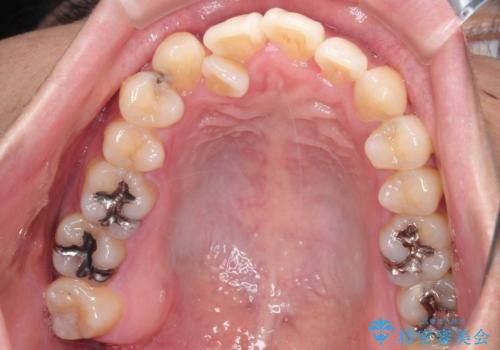

デコボコの量が多かったため上下左右4を抜歯してワイヤー矯正で治療を行いました。

正面から見たときに右上2が全く見えないくらい、右上2が後ろに引っ込んでいる状態でしたが綺麗に並べる事が出来ました。